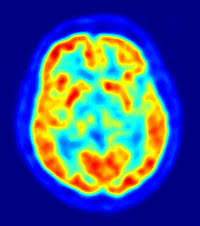

PET scan uses radiation, or nuclear medicine imaging, to produce 3-dimensional, color images of the functional processes within the human body. PET stands for positron emission tomography. The machine detects pairs of gamma rays which are emitted indirectly by a tracer (positron-emitting radionuclide) which is placed in the body on a biologically active molecule. The images are reconstructed by computer analysis. Modern machines often use a CT X-ray scan which is performed on the patient at the same time in the same machine.

Detecting positrons - A PET scan detects the energy emitted by positively-charge particles (positrons). As the radiotracer is broken down inside the patient's body positrons are made. This energy appears as a 3-dimensional image on a computer monitor.

The image - The image reveals how parts of the patients body function by the way they break down the radiotracer. A PET image will display different levels of positrons according to brightness and color.

When the image is complete it will be examined by a radiologist who reports his/her findings to a doctor. A radiologist is a doctor who specializes in interpreting these types of images, as well as MRI scanCT scan, Ultrasound and X-ray images.